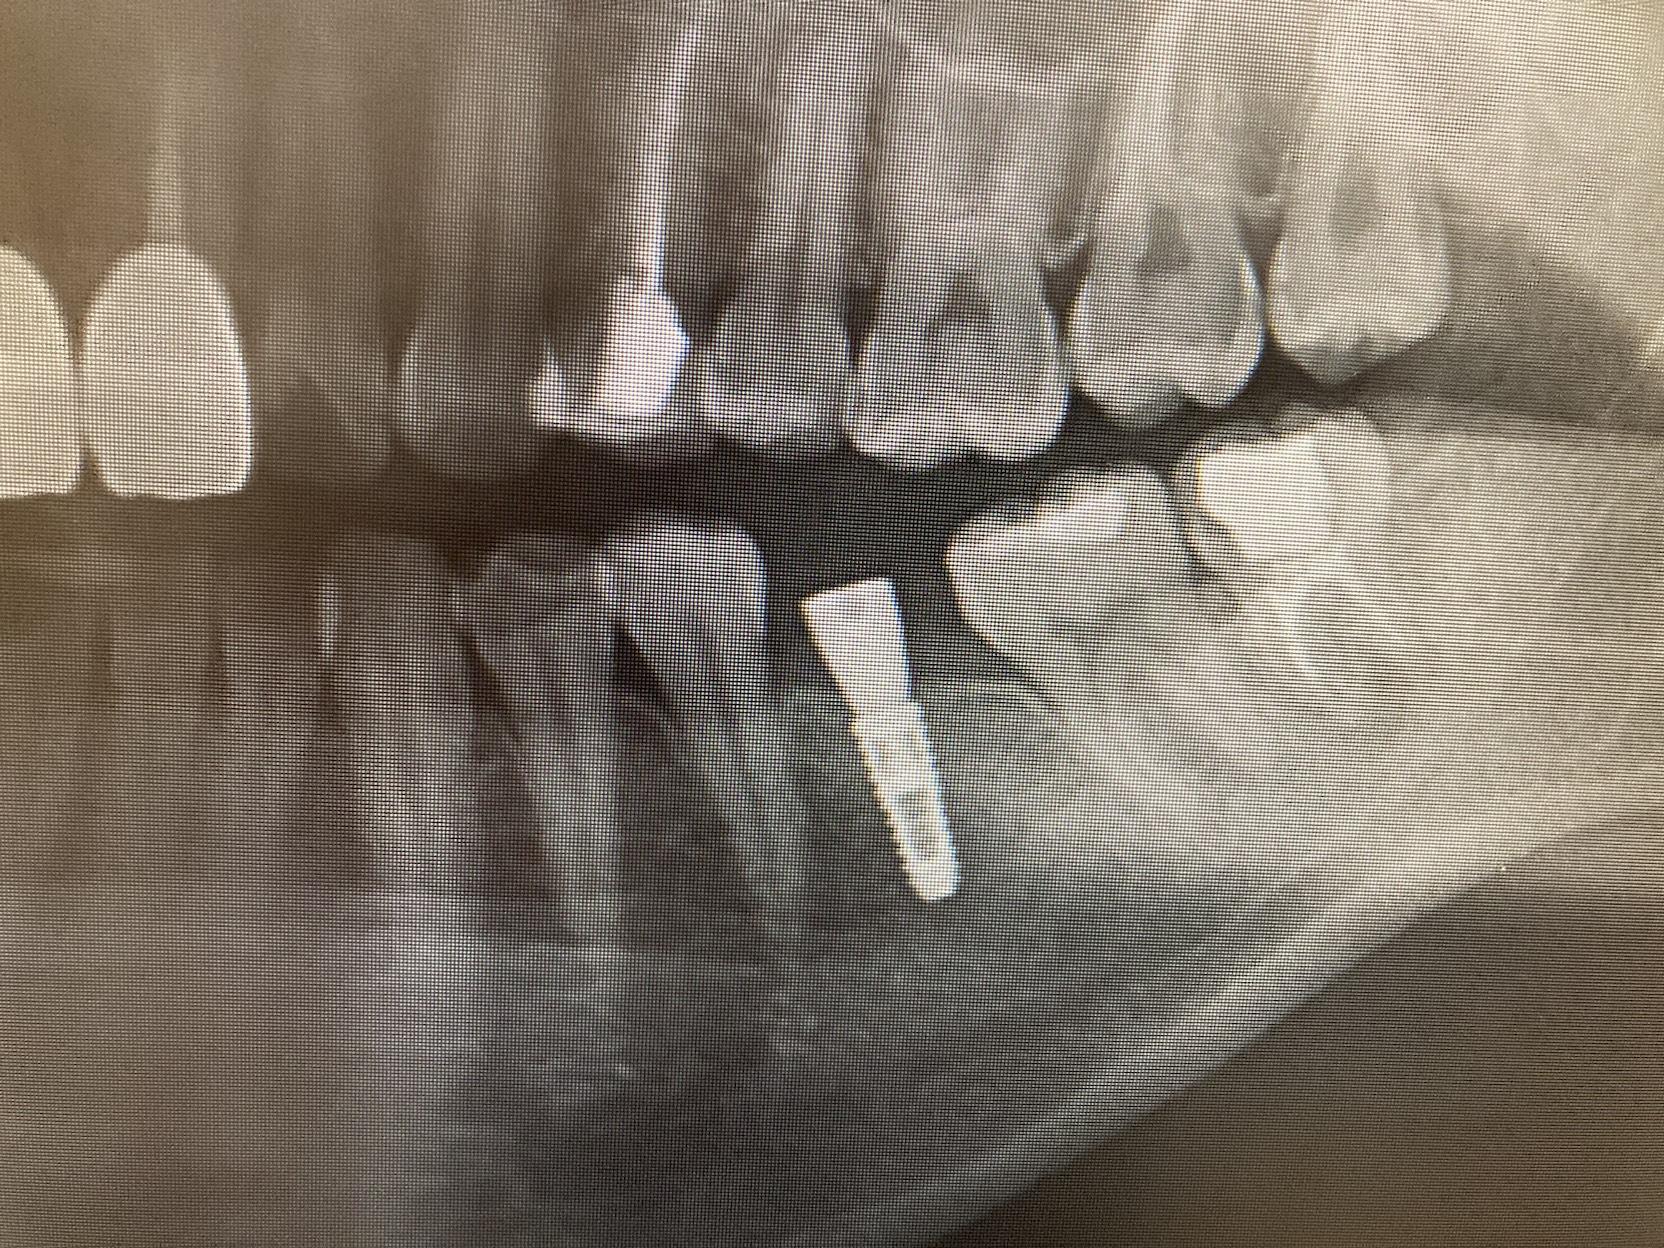

CASE 06

BEFORE

▶

AFTER

30代。 奥歯を失ってしまい、「しっかりと噛めるようになりたいが、健康な両隣の歯を削る『ブリッジ』や、取り外しの『入れ歯』には抵抗がある」とのことでご来院。